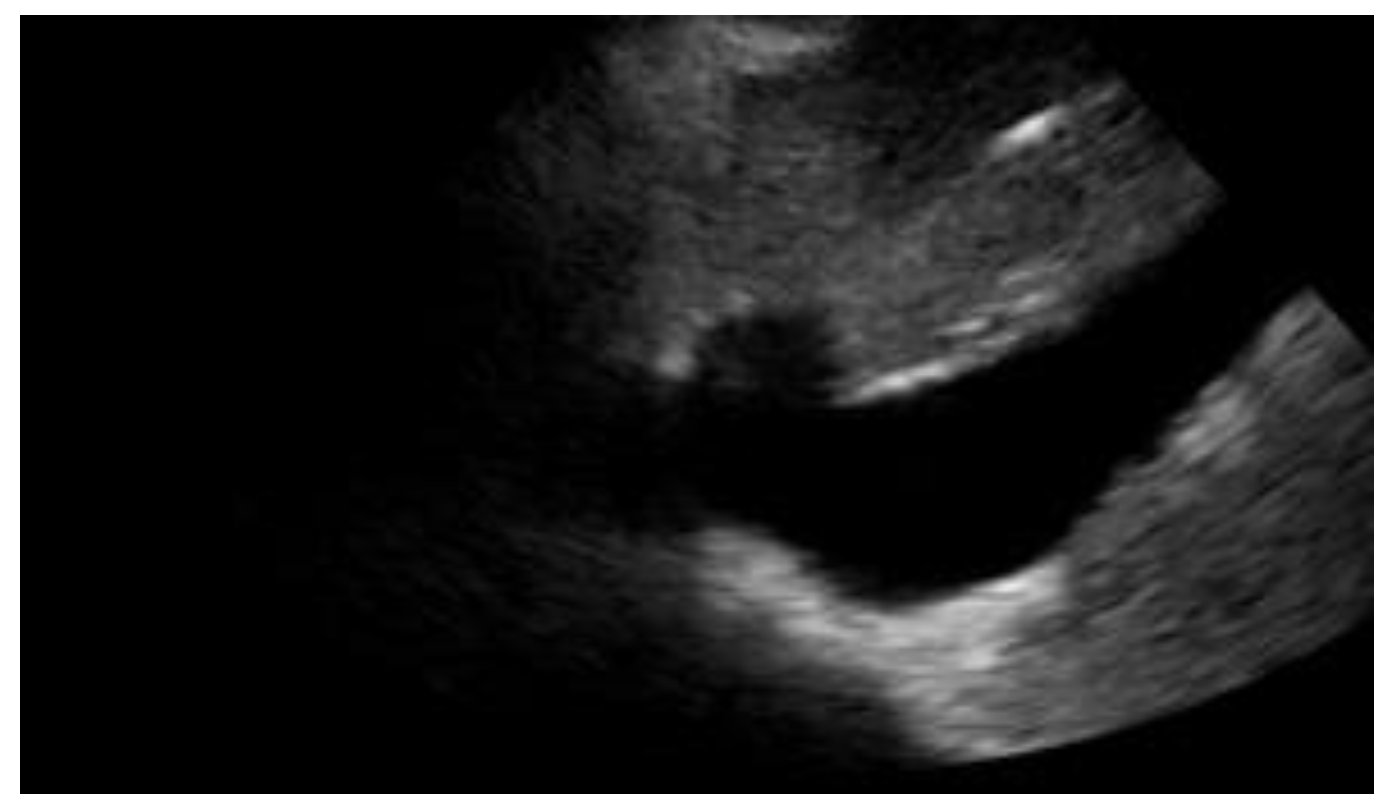

| Pneumonia | Consolidation, air bronchogram sign (Figure 8) |